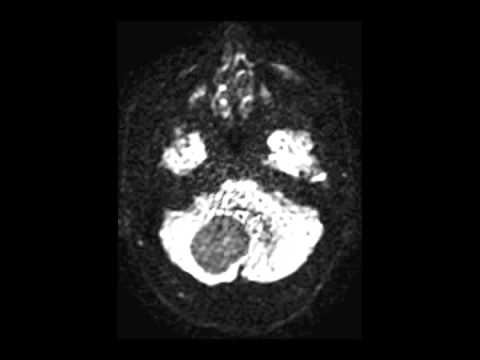

Hellow guys, Welcome to my website, and you are watching Suboccipital Craniotomy for Resection of a Fourth Ventricular Hemangioblastoma. and this vIdeo is uploaded by Barrow Neurological Institute at 2022-05-24T16:45:28-07:00. We are pramote this video only for entertainment and educational perpose only. So, I hop you like our website.